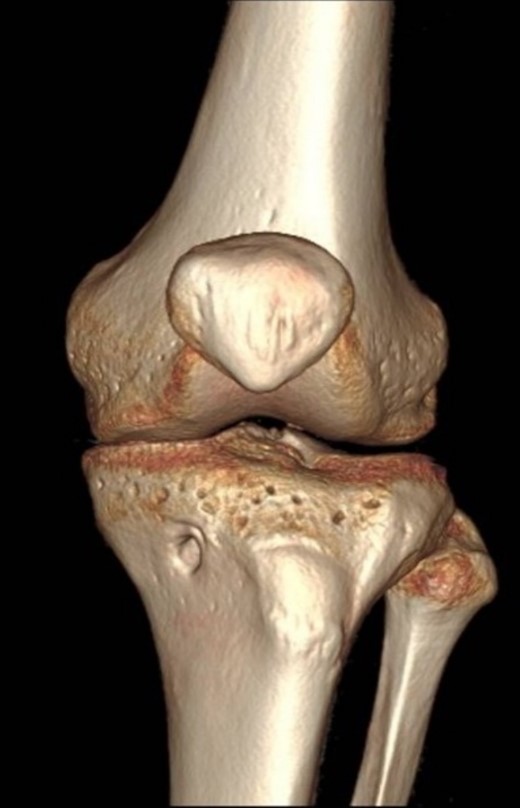

A 23-year-old male veterinarian presented to our out-patient department postright ACL reconstruction with hamstring autograft, PHMM tear by all-inside repair via sMCL pie-crusting technique, and lateral extra-articular tenodesis (modified Lemaire) in June 2023. A preoperative plain radiograph of the right knee revealed no evidence of HO (Fig. 1). No evidence of heterotopic ossification was detected in the right knee on plain radiographs taken 2 weeks postsurgery. (Fig. 2). Five months postsurgery, plain radiographs revealed new bone formation at the medial femoral condyle, precisely where the sMCL femoral origin was located (Fig. 3). The patient was asymptomatic and continued with rehabilitation. Seven months after the surgery, the patient started to complain of pain and clicking sensations when the right knee was flexed beyond an angle of 130°. Magnetic resonance imaging revealed consolidation of the newly formed bone, leading to a diagnosis of HO post-sMCL pie-crusting (Fig. 4). Nine months following surgery, the patient began to feel a bony mass on the medial side of the right knee. A plain radiograph and computed tomography (CT) scan revealed the complete formation of a bone island (Fig. 5). The past surgical history of this patient revealed that he had undergone left knee ACL reconstruction with hamstring autograft in December 2021, which failed and was complicated by a PHMM tear. The patient had presented to our facility for a revision. A revision ACL reconstruction was done using a bone-tendon-bone (BTB) autograft and PHMM tear all-inside repair via the sMCL pie-crusting technique in February 2022. A 2-year follow-up of the left knee, including physical examination and 3D-CT scans (Fig. 6), revealed no symptoms or signs of HO, although the same technique of sMCL pie-crusting was employed. Our patient suffered no head trauma during treatment. Past medical, drug, allergy, family, social histories, and reviews of systems were irrelevant to our case.

To our knowledge, this is the first case to report the occurrence of HO post-sMCL pie-crusting. HO is a new bone formation within the soft tissue and has been documented in the literature as a rare complication of ACL reconstruction using a BTB autograft [12]. HO is known as a complication of different conditions, including central nervous system damage or trauma, musculoskeletal trauma, burns, and certain genetic diseases [13]. Our patient lacked identifiable causative factors for HO, and it is unclear why he developed it in the right knee, while there was no HO in the left knee, although the same technique of sMCL pie-crusting was used. During arthroscopic PHMM tear repair, sMCL pie-crusting is commonly used to widen joint space, facilitate the repair, and avoid chondral injuries [14, 15]. In our technique of sMCL pie-crusting, we initially mark the medial epicondyle, and an 18-gauge needle is used to puncture the skin 1.5-cm posterior and slightly distal to this point. The needle is repetitively inserted and withdrawn from the anterior to posterior aspect of the sMCL while applying gentle valgus stress and flexing the knee 20°–30°. An arthroscopic camera was used in the medial compartment to confirm the appropriate opening of joint space.